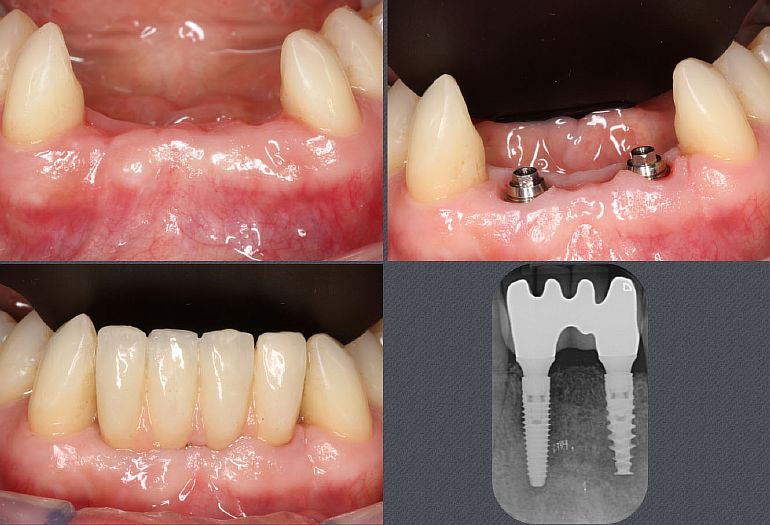

Необходимо четко различать два аспекта лечения имплантата: размещение самого зубного имплантата, с одной стороны, и соединение с этим имплантатом протеза с «опорой на имплантате», с другой. Сам имплантат представляет собой титановый винт, выступающий в роли искусственного корня. Только этот винт бесполезен для пациента и становится полезным только тогда, когда к нему подключен протез (коронка или мост, в зависимости от обстоятельств). Затем пара имплантат-протез выполняет свою жевательную и эстетическую роль.

Фактически, для полной замены зуба имплантатом требуется как минимум два сеанса: хирургический сеанс (установка винта) и сеанс протезирования.

С точки зрения комфорта, во-первых, нет заметной разницы между естественным зубом и имплантатом, так что очень быстро пользователь забывает, какой зуб его, а какой восстановлен имплантатом.

С эстетической точки зрения это теперь зависит от нескольких факторов: сложности исходной клинической ситуации, а также опыта работников. Когда все идеальные условия соблюдены, не может быть эстетической разницы между зубным имплантатом и натуральным зубом.